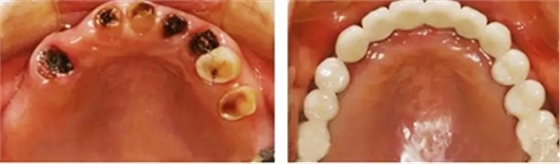

答:種植牙與傳統(tǒng)義齒比較,具有很多優(yōu)點(diǎn)。它外形逼真、美觀;穩(wěn)定性好,咀嚼功能大大優(yōu)于傳統(tǒng)活動(dòng)假牙;無需磨削缺牙旁邊的好牙,最大程度地保護(hù)了患者的健康牙齒;體積小,最大限度地減少假牙對(duì)發(fā)音的影響;舒適衛(wèi)生;既不怕冷,又不畏酸;使用方便。無論是蛀牙爛得過深,還是外傷造成牙齒需要拔掉,種植牙是目前最舒適最美觀的選擇,讓你再不用戴“看著假,戴著也假”的假牙。